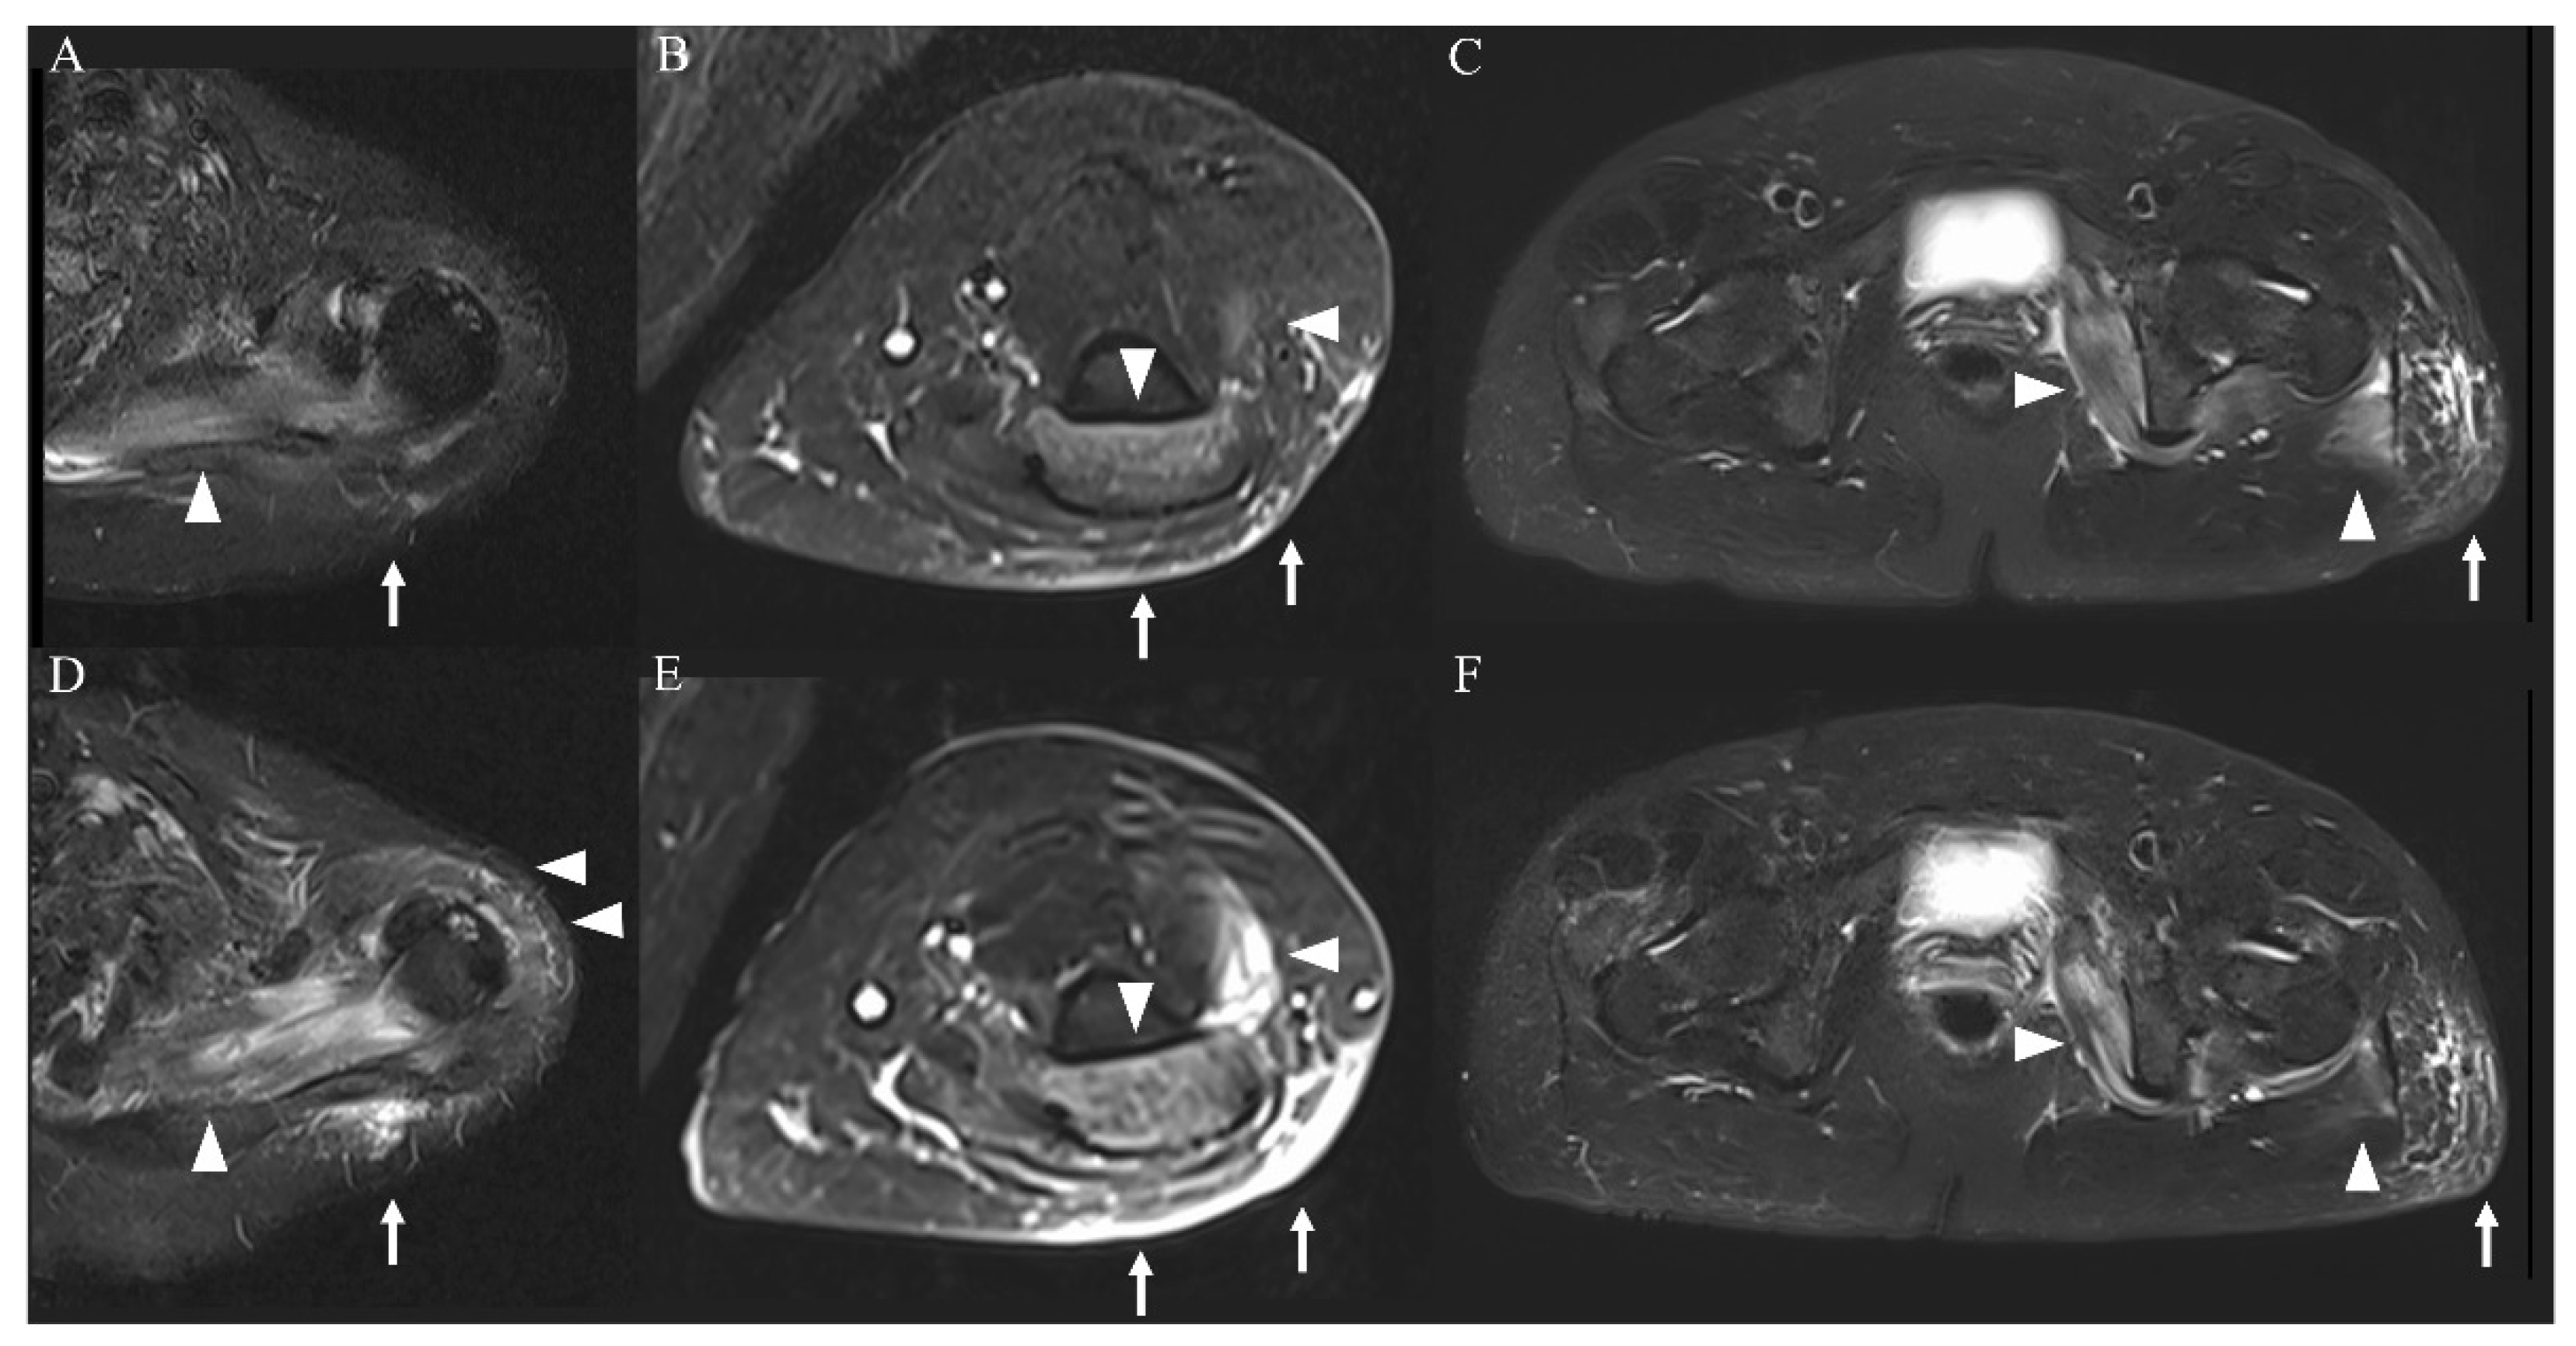

On admission, the patient was conscious; her body temperature was 37.7 °C, her heart rate was 72 beats/minute, her blood pressure was 129/68 mmHg, and her percutaneous oxygen saturation was 100%. A physical examination showed mild bilateral weakness of the iliopsoas muscles (Medical Research Council (MRC) scale 4/4) and no evidence of weakness of the deltoid, biceps, or triceps muscles (MRC scale 5/5); tenderness; edema; or rash. Laboratory findings showed that her white blood cell count was 7400 μL, concentration of creatine kinase (CK) was 9816 U/L, CK-MB was 106 U/L, myoglobin was 1802 ng/mL, aspartate transaminase was 164 U/L, alanine transaminase was 56 U/L, blood urea nitrogen was 13.2 mg/dL, serum creatinine was 0.56 mg/dL, and C-reactive protein was 4.45 mg/dL (Table 1). Urinalysis showed 3+ blood. All other laboratory findings, including electrolyte concentrations and antibodies associated with myositis, were unremarkable. Thyroid function was normal. Real-time reverse-transcriptase polymerase chain reaction for COVID-19 was negative on admission. The IL-6 concentration on the second day of admission had increased. This elevated IL-6 concentration decreased to the normal range and tumor necrosis factor (TNF)-α and IL-1β concentrations remained within the normal range over the disease course (Figure 1). MRI of the limbs showed hyperintensity in the left dominant bilateral triceps brachii, left supraspinatus, deltoid, internal obturator, and gluteal muscles, and subcutaneous fluid retention was observed on short-tau inversion recovery images (Figure 2A–C). The iliopsoas muscles could not be scanned during MRI of the extremities because they were outside of the scan range. An electromyogram (EMG) of the affected muscles indicated no evidence of positive sharp waves or fibrillation at rest and small and partly polyphasic motor unit potentials in voluntary contraction. Transthoracic echocardiography, a pulmonary function test, and whole-body computed tomography imaging were unremarkable.

Figure 2.

MRI of the extremities (short-tau inversion recovery images). Imaging on admission showed a high-intensity area in the left dominant bilateral triceps brachii, left supraspinatus, deltoid, internal obturator, and gluteal muscles ((A–C), arrowheads) and subcutaneous tissue ((A–C), arrows). These findings were more severe in the upper limb muscles ((D,E), arrowheads and arrows) and were attenuated in the lower limb muscles ((F), arrowheads and arrows) on day 4 of hospitalization.

The patient was admitted and treated with intravenous normal saline for rhabdomyolysis and loxoprofen for myalgia. On day 3 of hospitalization, her weakness and myalgia had completely disappeared. However, the next day, follow-up MRI showed slight exacerbation of the hyperintensity of the left upper limb muscles and attenuation of the hyperintensities of the lower limb muscles (Figure 2D–F). Most affected muscles were enhanced, and only the left supraspinatus muscle had homogeneous enhancement (Figure 3A–C). On day 5 of hospitalization, weakness of the left supraspinatus and deltoid muscles (MRC scale 5/4) developed, with swelling and tenderness of the left supraspinatus. A nerve conduction study (NCS) showed that the compound muscle action potentials (CMAP) of the right and left deltoid muscles were 9.210 and 2.540 mV, respectively. MRI on day 8 of hospitalization showed attenuation of the hyperintensity of all muscles. The weakness gradually subsided and then disappeared on day 10 of hospitalization. Electrolytes and renal function were within normal limits during hospitalization. CK, myoglobin, and liver enzyme concentrations improved over the course of hospitalization, and the CK concentration returned to normal on day 10 of hospitalization. The patient was discharged the next day.